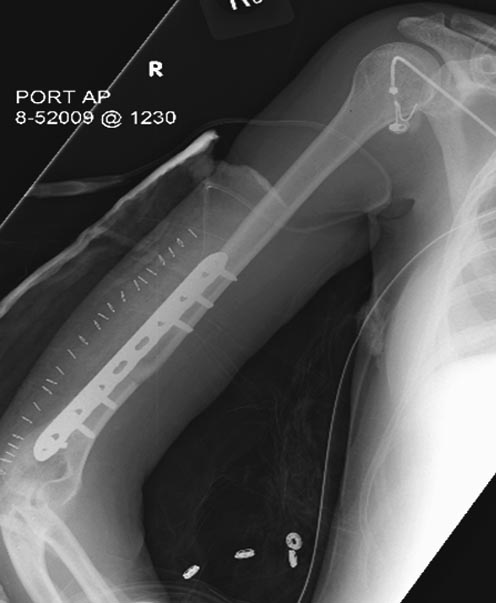

Раны в области коленного сустава и на плече до сих пор чистые, остаются

открытыми. Отсутствует признаки инфекции, решили превратить недостаток в

преимущество, т.е. фиксировать через открытые раны пластинами.

На 11й день фиксация плеча также пластиной.